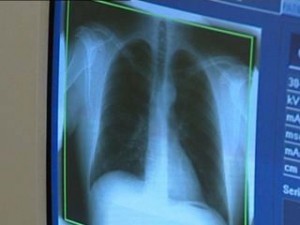

Tájékoztatjuk a község lakosságát, hogy a 2013-as évben a Jósa András Oktató Kórház szervezésében ismét lesz Nyírkarászon ingyenes tüdőszűrő vizsgálat.

A tüdőszűrésen való megjelenés 30 éves kortól KÖTELEZŐ és INGYENES!